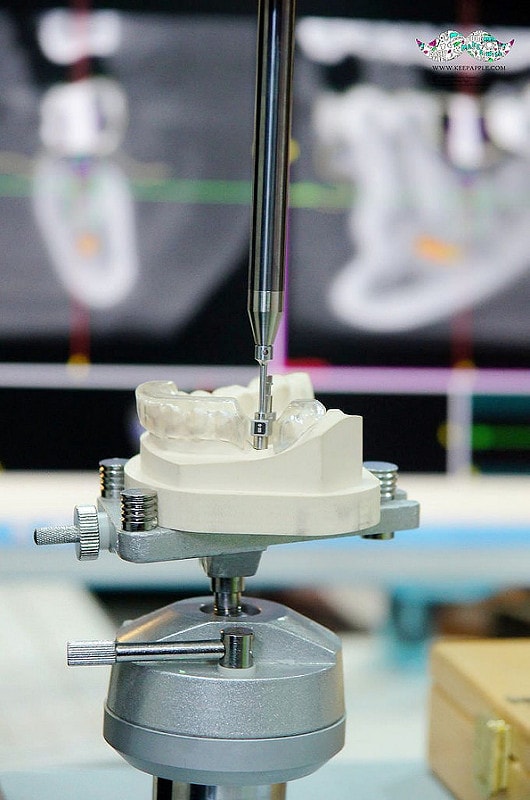

主要就是運用這台GPS導航植牙( i – Max 寰視導引植牙系統)的機器

這套系統最重要的目的就是讓牙醫師在術前先進行過一次模擬植牙手術

利用電腦3D定位精準演算分析出植牙位置與角度

看要從哪個角度、深度進行植牙~

在經過預先演練以後牙醫師在真正動手術時,

既能節省時間又能大幅增加植牙成功率